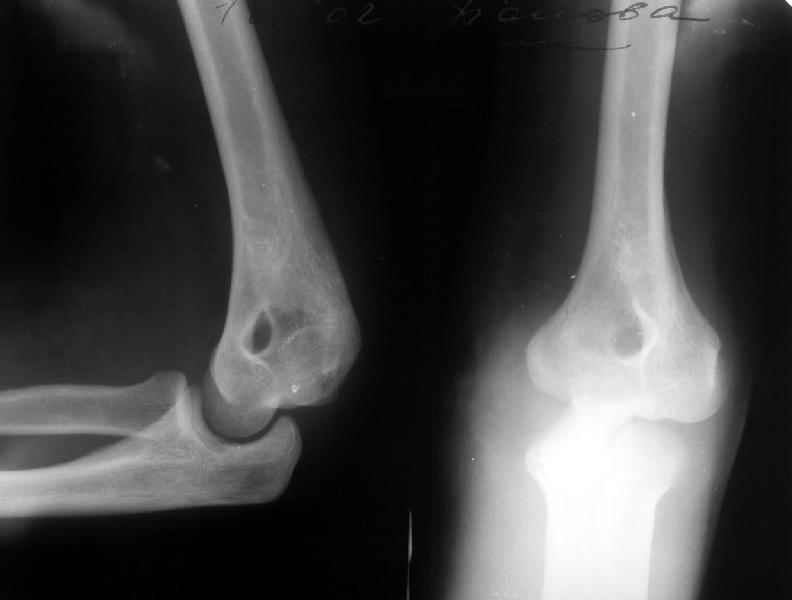

Пациентка 48 лет при падении с 5 этажа получила травму 28.04.02. Среди прочих повреждений был открытый задний вывих предплечья (см. снимок). Он был сразу вправлен, рана 6 см по внутренней поверхности

области локтевого сустава была обработана по месту первичного поступления. К нам поступила 7.05.02. Рана зажила первичным натяжением. Вчера, то есть через три недели после вправления, сняли повязку для разработки движений. Выявлено, что предплечье легко смещается медиально, и вправляется. Движения в локтевом суставе покаплохие. Свежие снимки и в правильном положении, и в подвывихе прилагаются. Вопрос - что делать? Продлить иммобилизацию гипсом? Идти на ревизию и восстановление внутренней боковой связки? Наложить шарнирный аппарат?Заранее спасибо.-- Best regards, Alexander N. Chelnokov